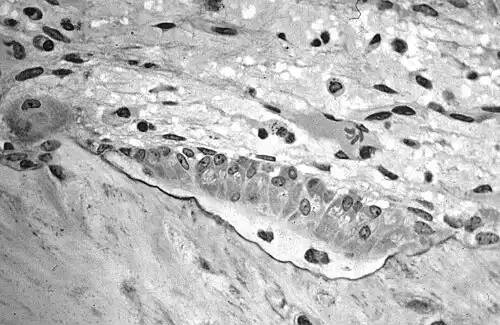

به بافت پایهٔ استخوان که هنوز آهکی نشده باشد، استخوان واره یا استئوئید ( انگلیسی: Osteoid ) می گویند.

یاخته های چندهسته ای به نام استخوان ساز ( استئوبلاست ) ماده پروتئینی از جنس کلاژن را می سازند که به آن استخوان واره می گویند. سپس مواد معدنی بر روی استخوان واره سوار شده و ماده بنیادی استخوان ( ماتریکس ) را می سازد. استخوان سازها همچنین هورمون هایی از خود ترشح می کنند که از طریق آنها می توانند با سلول های دیگر و با بافت های دیگر بدن ارتباط برقرار کنند و بر روی آنها تأثیر بگذارند.